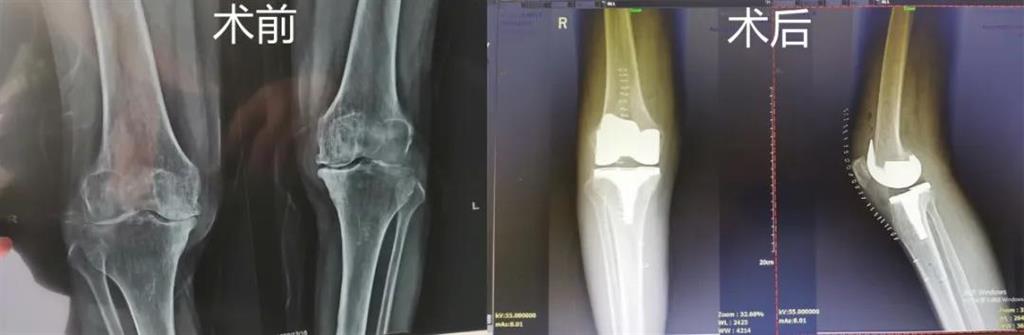

和平國際醫(yī)院副院長、骨科中心主任劉丹在診斷后發(fā)現(xiàn),老人雙側(cè)膝關(guān)節(jié)患有骨性關(guān)節(jié)炎,右側(cè)膝關(guān)節(jié)較為嚴(yán)重,而且關(guān)節(jié)磨損嚴(yán)重關(guān)節(jié)間隙基本消失。

經(jīng)過進(jìn)一步檢查后,劉丹帶領(lǐng)團(tuán)隊(duì)在計(jì)算機(jī)導(dǎo)航系統(tǒng)的輔助下,為老人實(shí)施了右側(cè)全膝關(guān)節(jié)置換手術(shù)。術(shù)中出血明顯減少,術(shù)后疼痛腫脹等反應(yīng)輕微,畸形矯正力線恢復(fù)理想,而且功能恢復(fù)快速,術(shù)后四天就可以下地行走。

據(jù)劉丹主任介紹,計(jì)算機(jī)導(dǎo)航膝關(guān)節(jié)置換術(shù)可以避免打開股骨髓腔,從而明顯減小手術(shù)創(chuàng)傷減少術(shù)中出血,能夠更精準(zhǔn)地從三維角度調(diào)整手術(shù)截骨方向,恢復(fù)肢體對(duì)線,并能進(jìn)行精確的軟組織平衡,從而使患者獲得良好的術(shù)后功能恢復(fù)。